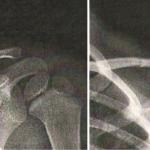

Hygroma dans un contexte d’amputation bilatérale des membres inférieurs

Une enfant de 11 ans est amputée des membres inférieurs à la suite d’un choc toxique survenu dans le contexte d’une...